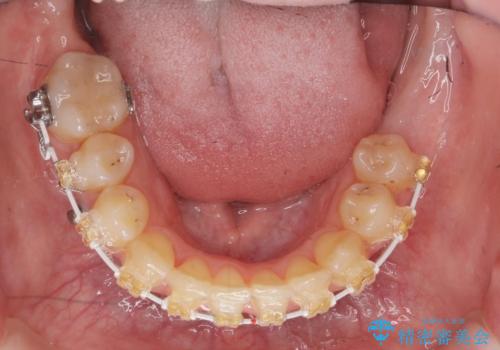

左下の親知らず、左上の小臼歯が残根状態で一本抜いたほかは抜かずに矯正しました。

①保存不可能な歯は抜歯しそのすき間を矯正で閉じる

という、予算がかからないように歯を保存する治療計画を立てました。

予算的に右下の一番奥のインプラントは難しかったため、できる限り対応しました。

途中矯正後に妊娠出産、育児等で2年以上中断を経た後虫歯治療の続きを行いました。最終的に治療完了まで行い状態は安定しています。